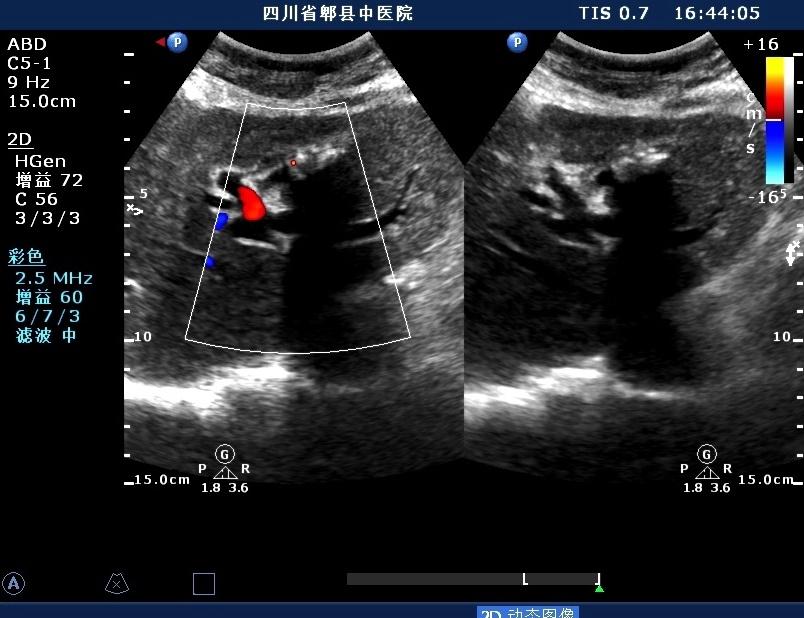

超声如图:胆总管及肝内胆管扩张,呈“平行管征”,胆总管胰腺段可见疏松强回声团堆积,后方可见淡淡声影,左肝外叶胆管内亦可见数个强回声团堆积,后方伴声影。 肝脏及胆总管

扩张的胆总管

胆总管胰腺段结石